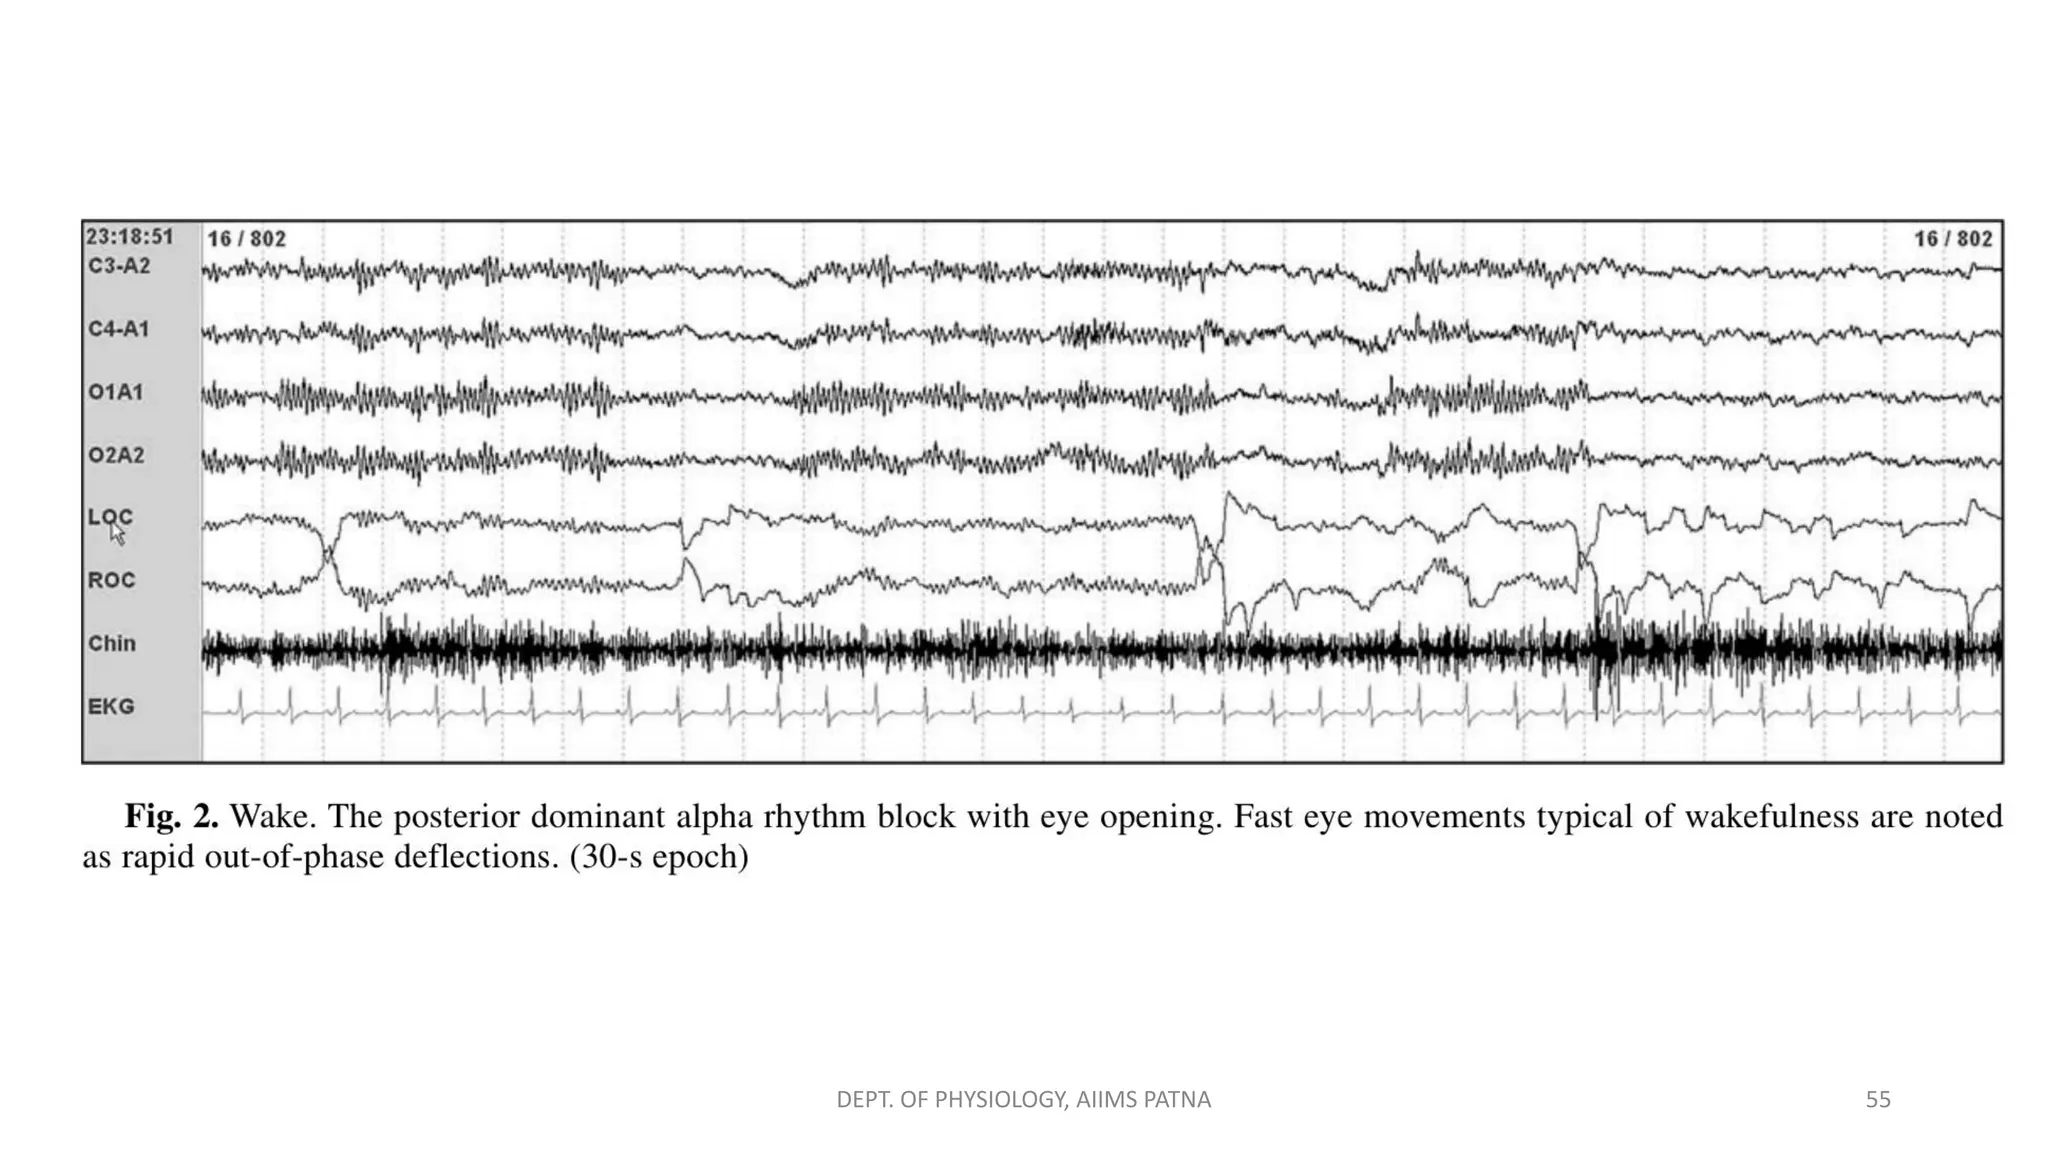

Wakefulness – W (Eyes open)

EEG → high-frequency, low-voltage activity (chiefly beta and alpha

frequencies) without the rhythmicity of alpha rhythm ⇒ indicative of

the unique activity of individual cortical neurons

EOG → Rapid eye movements (initial deflection is less than 500ms)

and eye blinks (vertical movements 0.5–2 Hz), Reading eye

movements

EMG → Chin EMG relatively increased compared with that during

sleep - high-frequency activity

54

DEPT. OF PHYSIOLOGY, AIIMS PATNA

DEPT. OF PHYSIOLOGY, AIIMS PATNA 55